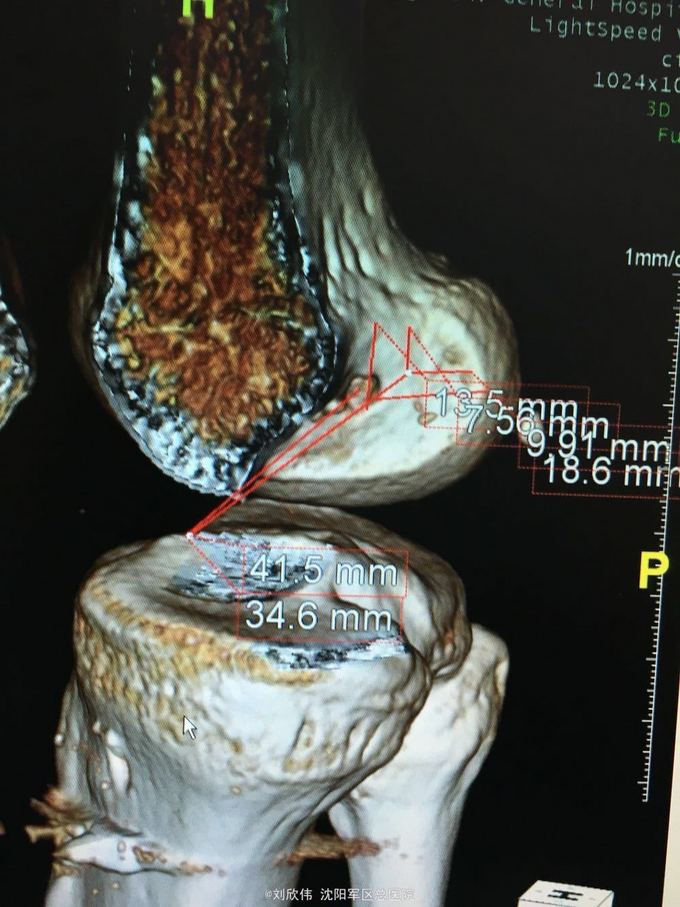

右膝前交叉韧带断裂 右膝半月板损伤 手术方法如题,直接上图

这个病例术后汇付的非常快 值得讨论的是acl重建时,股骨隧道内口的选择还是很有讲究的,目前从AM入路建立隧道点很热,但是,说是解剖重建,术中确实很多人选的点确是等长点,由于我们LARS韧带也做,所以这点体会有味深刻 解剖点的位置相比等长点,是比较偏下的(屈膝90°,关节镜操作时的角度而言),偏向平台关节面,这样虽然解剖,但会导致股骨隧道长度过短。需要注意